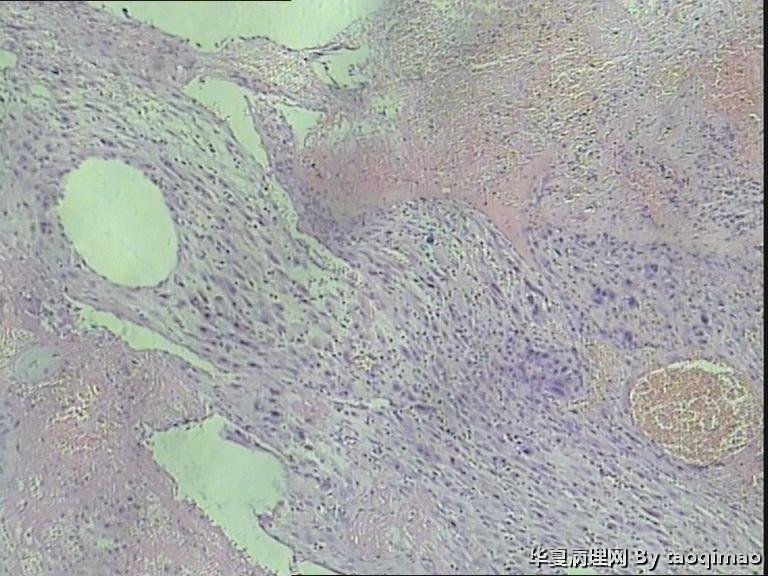

• 功血,滋养细胞浅肌层?图4

图4

上一组图是全子宫切除后宫内膜及浅肌层的切片,取材时发现在子底及后壁有暗紫色血凝块与宫内膜分界不清

追问病史 除外绒癌 侵袭性葡萄胎